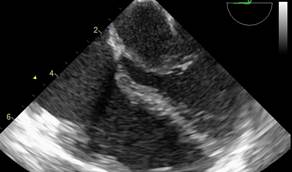

En subcostal 4 cámaras se observa CIA de 7 mm de diámetro con shunt de izquierda a derecha. (Figuras 2,3,4)